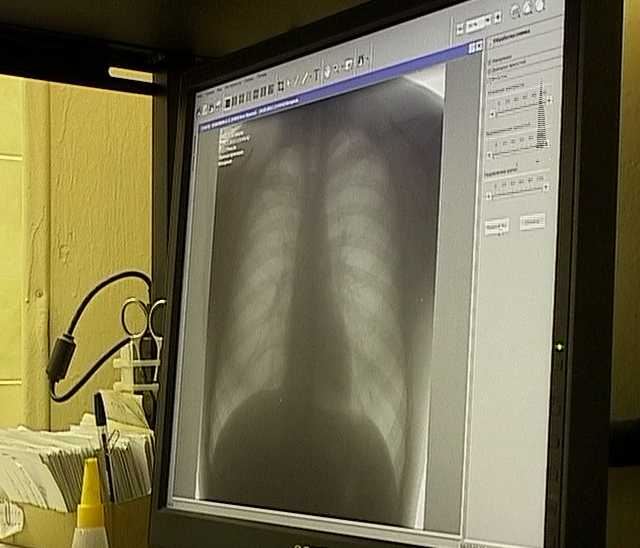

День борьбы с туберкулезом сюжет гтрк - фото презентация